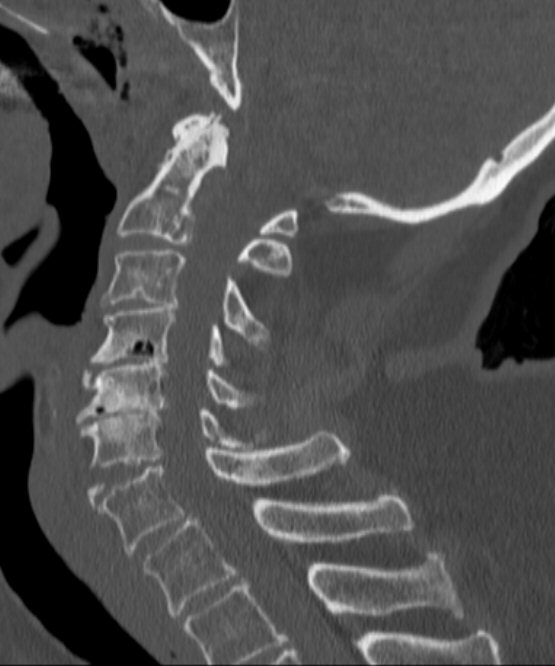

Distraktion mellan C6 och C7, opererades med bakre stag

Typiskt äldre patient med degenererad halsrygg som fallit på pannan berusad. DT med diskreta fynd, kan vara helt normal, visa extensions teardrop (se bilder nedan) eller distraktion i disk. Kan vara mycket instabil.